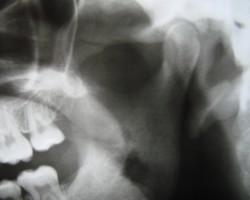

Kiefergelenkprobleme

Das menschliche Gebiss ist so stark, dass es einen

erwachsenen Mann halten kann. Aber wenn der Biss nicht stimmt

(»falsches Zusammenbeißen«), ist das gefährlich

für den gesamten Organismus. Den Biß zu bewahren ist

deshalb ein hohes Gebot der modernen Zahnmedizin.

Die Ursache für eine Störung des Kiefergelenks

und der Kaumuskulatur können u.a. Zahnfehlstellungen, Zahnfüllungen

und Zahnlücken, schlecht sitzender Zahnersatz oder traumatische

Einflüsse auf die Wirbelsäule sein. Auffällige

Symptome sind Muskelschmerzen, Kiefergelenkbeschwerden und Kiefergelenkknacken,

Schleifspuren an den Zähnen, zerstörte Zahnhälse

bis hin zu Schädigungen des Zahnhalteapparates.

Die zahnärztliche Untersuchung besteht aus

einer Analyse der Muskulatur, der Kiefergelenke und der Bisssituation

sowie einer Vermessung des Kiefergelenks. Die Bisssituation wird

zur Bestimmung der korrekten Bisslage in einen Bewegungssimulator

übertragen. Mit diesen Untersuchungen kann der Zahnarzt eine

aussagekräftige Diagnose stellen.